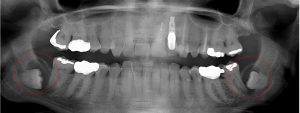

This 48 year old patient had all four 3rd molars extracted in his late 20’s. All four sites healed poorly and chronically infected bony defects remained. The upper right 2nd molar was extracted two years ago as a result of this chronic infection. The upper left 2nd molar must now be extracted because of a chronic periodontal infection moving around that tooth. Both lower molars are chronically infected and have a poor prognosis.